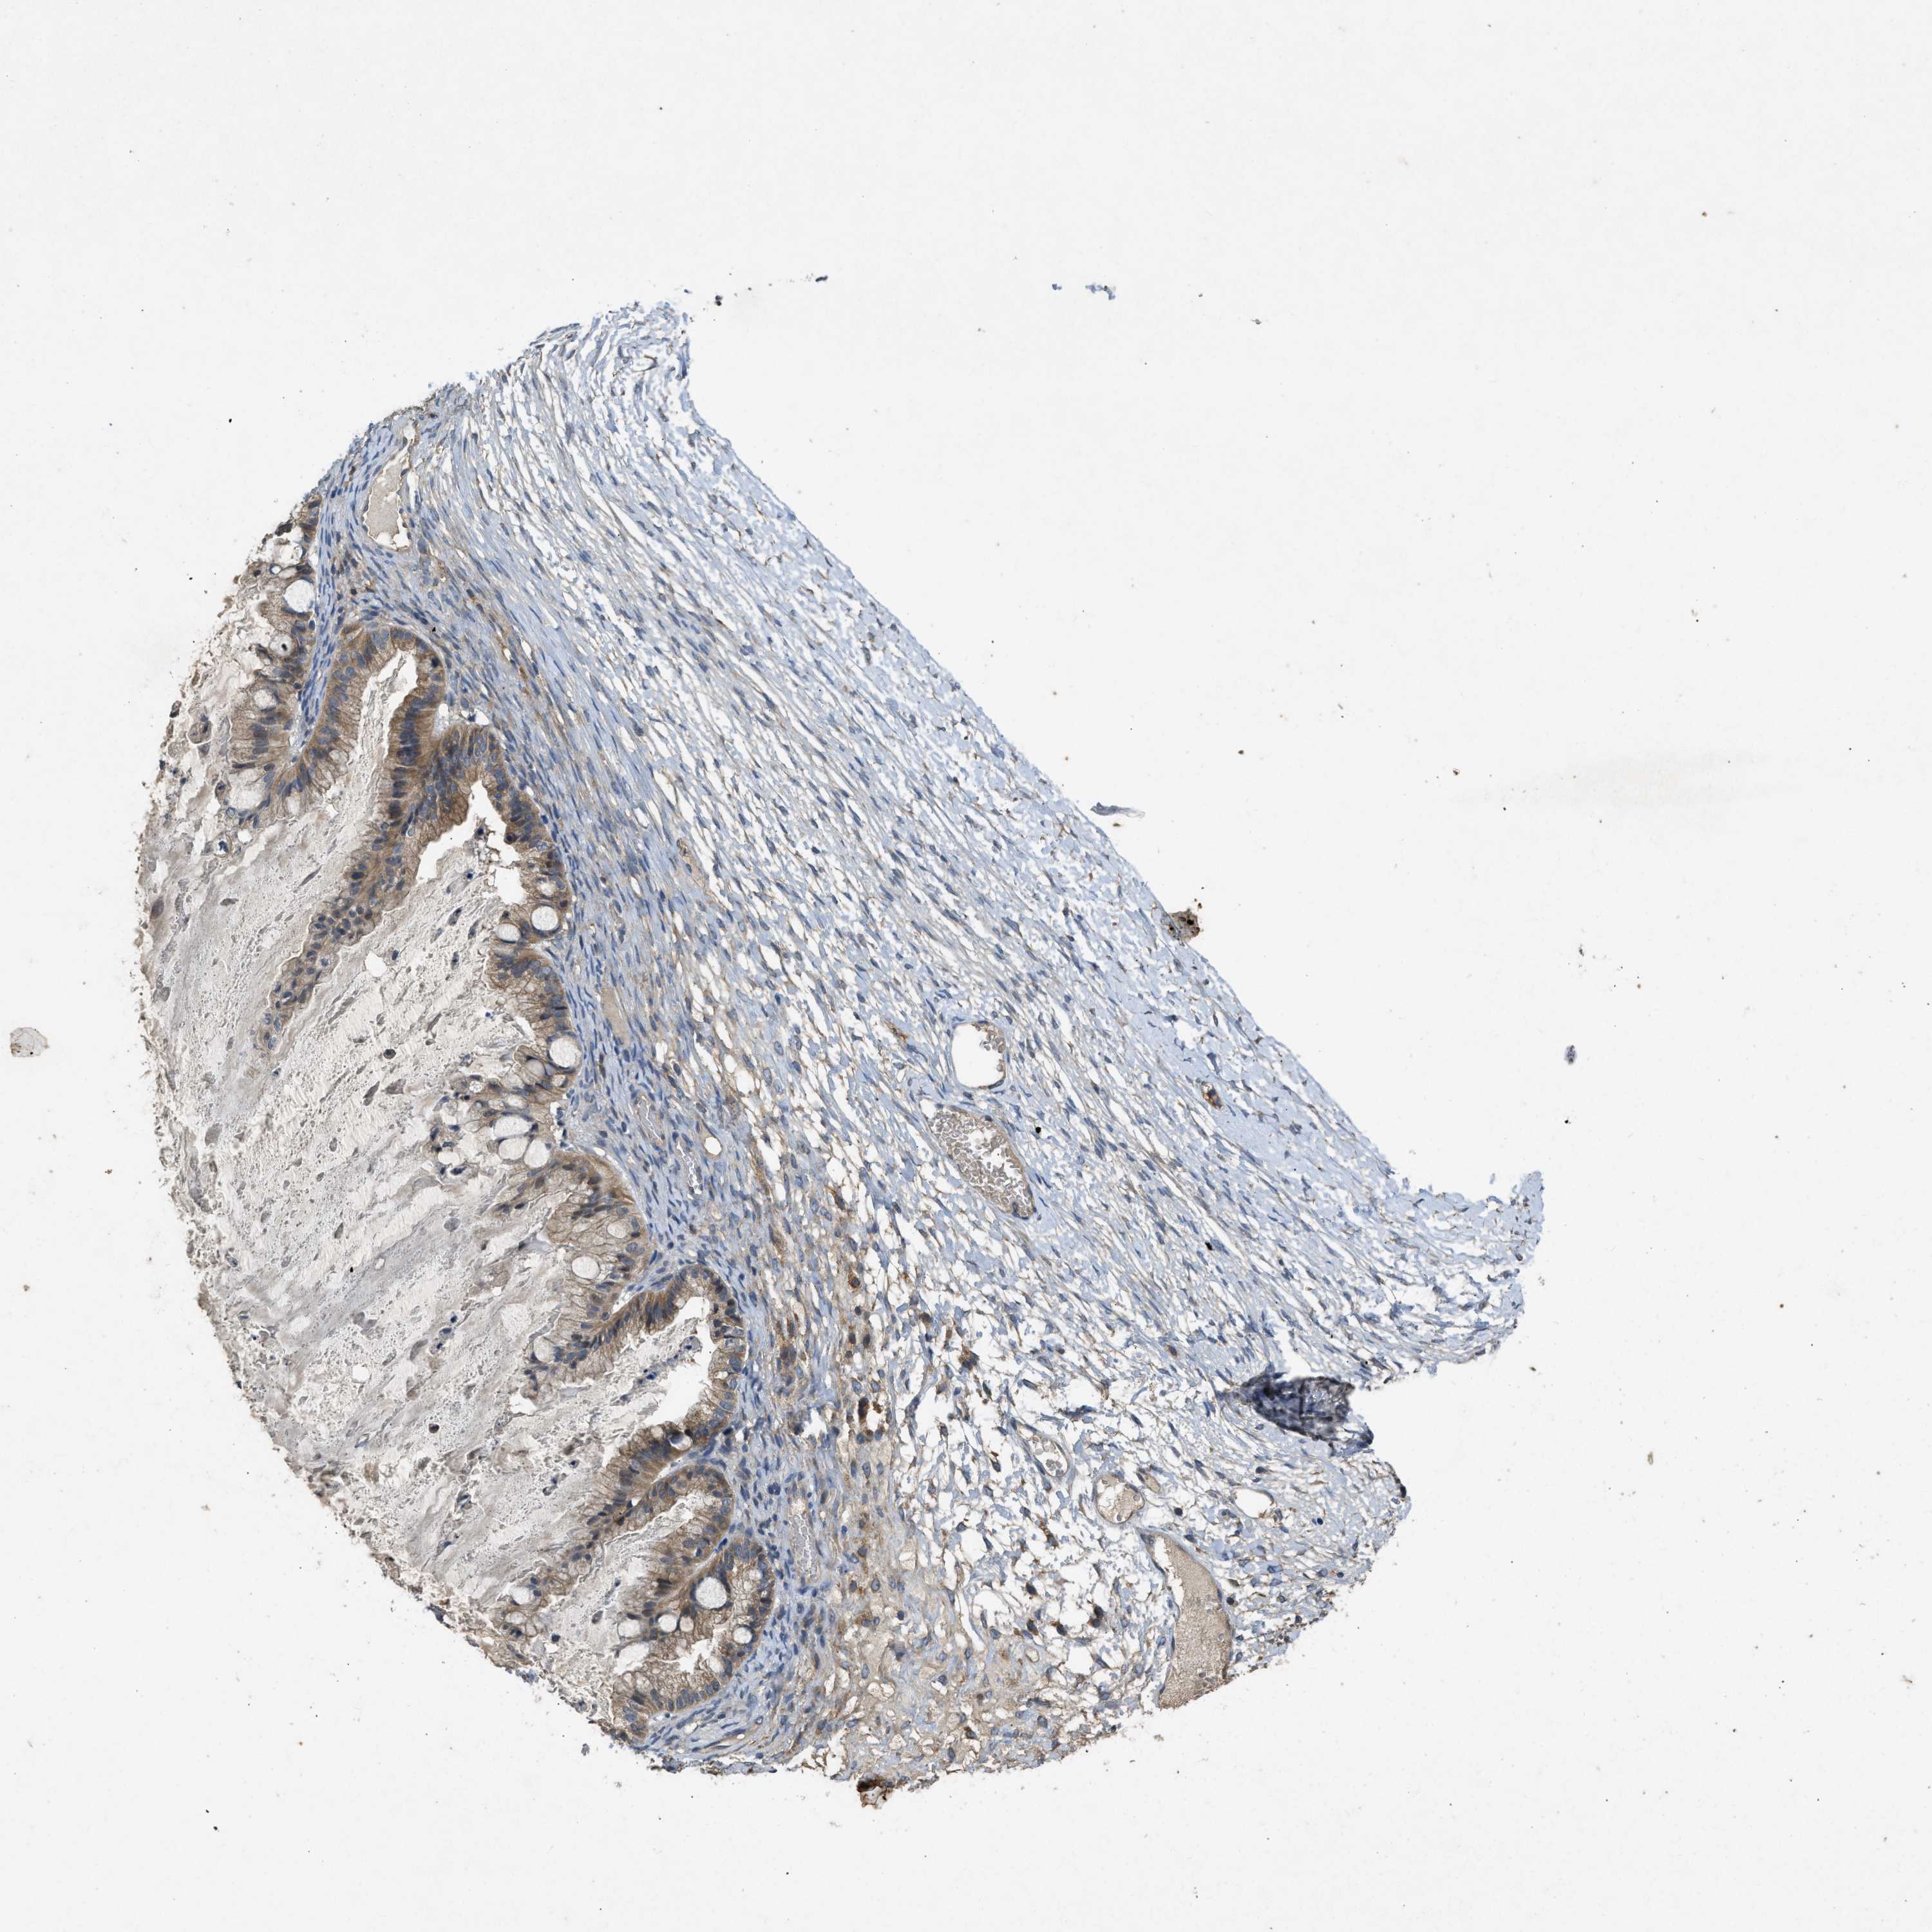

OVARIAN CANCER - Protein expressioni

A mouse-over function shows sample information and annotation data. Click on an image to view it in a full screen mode. Samples can be filtered based on level of antibody staining by selecting one or several of the following categories: high, medium, low and not detected. The assay and annotation is described here.

Note that samples used for immunohistochemistry by the Human Protein Atlas do not correspond to samples in the TCGA dataset.

Antibody stainingi

Antibody staining in the annotated cell types in the current human tissue is reported as not detected, low, medium, or high, based on conventional immunohistochemistry profiling in selected tissues. This score is based on the combination of the staining intensity and fraction of stained cells.

Each image is clickable and will lead to virtual microscopy that enables deeper exploration of all samples and also displays staining intensity scores, fraction scores and subcellular localization as well as patient and tissue information for each sample.

Antibody HPA012778

Antibody CAB018581

Cystadenocarcinoma, serous, NOS

Carcinoma, endometroid

Cystadenocarcinoma, mucinous, NOS

Carcinoma, NOS